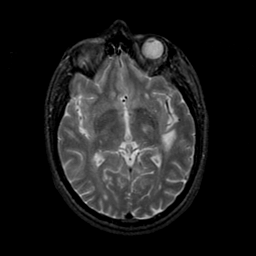

MR Study #23, January 26, 1992 -- Slice #24